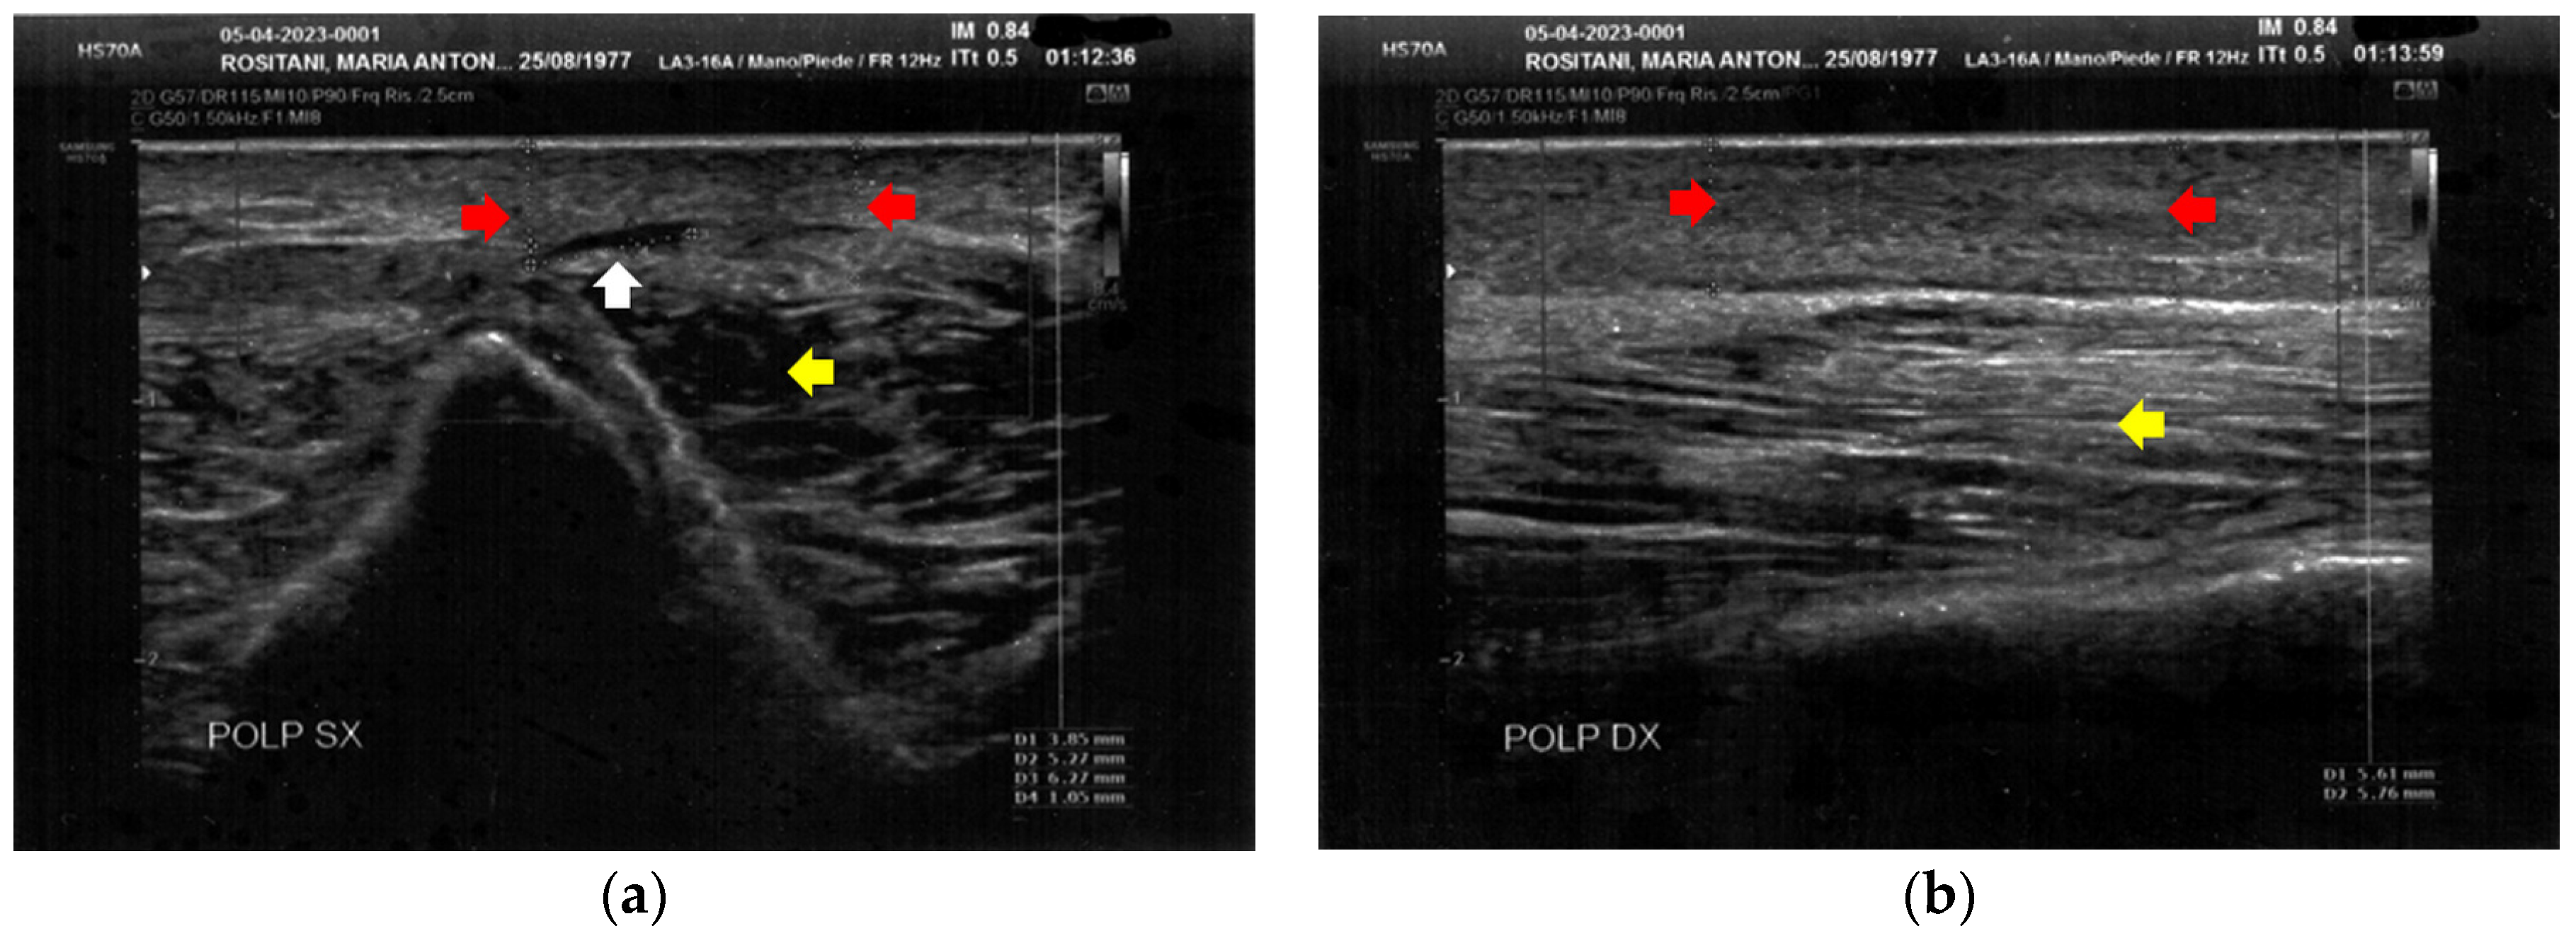

3.1. Basal Imaging Evaluations

3.2. Imaging Evaluations After the Treatment